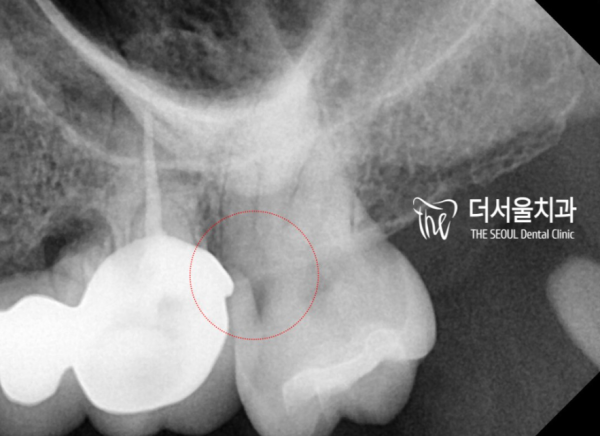

이렇게 방사선 사진을 통해서 충치의 범위가 확인되는데요.

신경과 가까운 위치에 근접해 있는 것으로 관찰이 됩니다.

신경치료를 해야 하는 상황입니다.

The extent of the cavity is confirmed by the radiographic image.

It is observed to be close to the nerve.

It's a situation where you have to do neurotherapy.